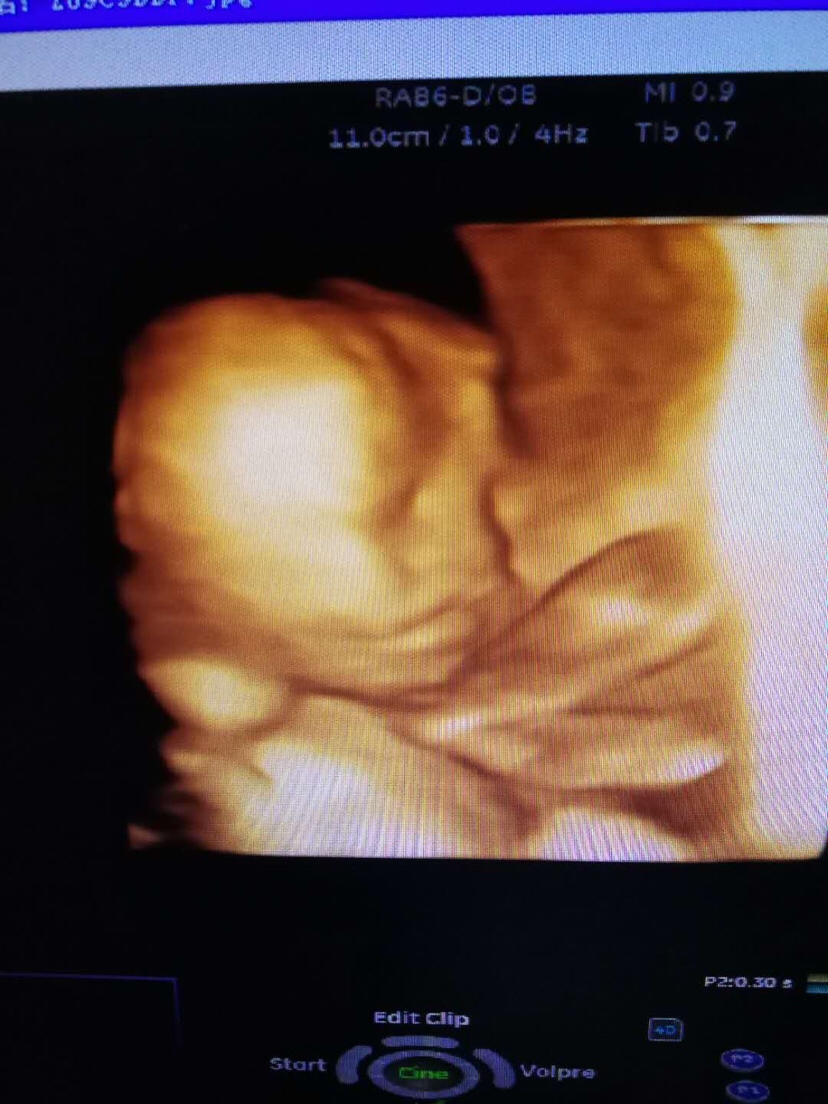

孕15周+2天

都那么大了还会胎停的吗?好怕

孕28周+1天

孕24周+3天

就感觉不到胎动了

[帖主]:就感觉不到胎动了